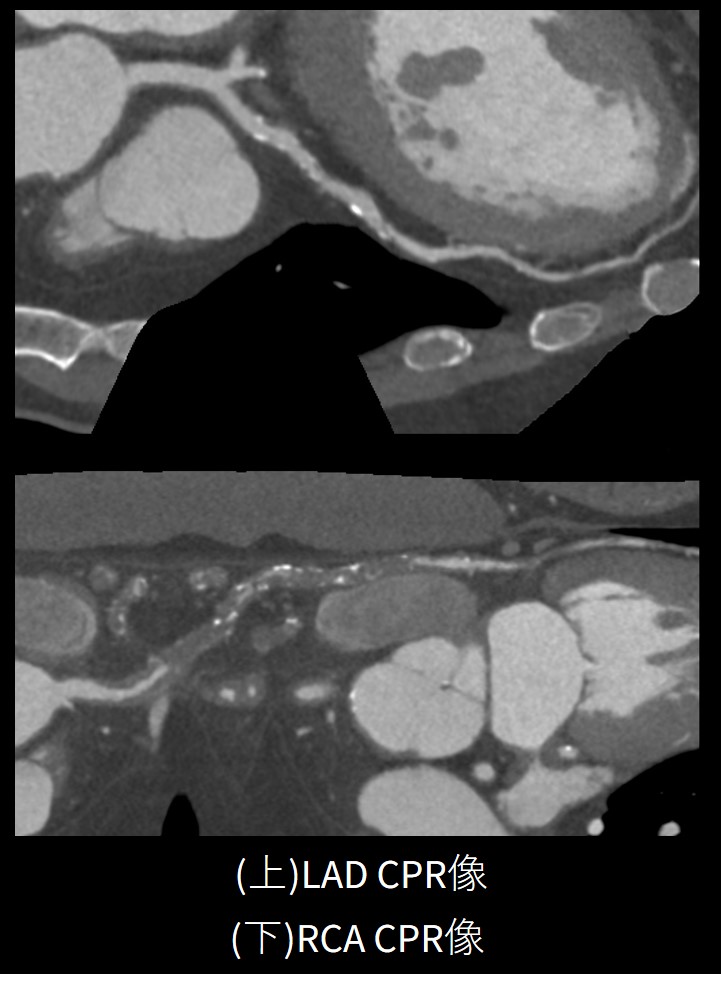

③不正脈・100kgの高体重症例

2段脈様に一定の間隔で不整脈がある上、体重100kgと高体重の患者様でした。レトロスペクティブに不整脈を削除してSSF2.0を掛けることで問題なく解析が出来ました。LADに50%程度の狭窄あり、RCAにはCTOが見られました。高体重者に対しても、最大853mAの線量をかけることができるため、コントラストの高い良質な画像が得られています。

Frontier_Kofukyoritsu08.jpg

Frontier_Kofukyoritsu091.jpg

Frontier_Kofukyoritsu092.jpg